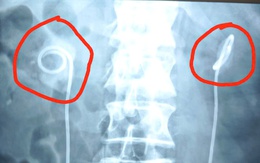

Vòng tránh thai ‘đi lạc’ vào bàng quang

Đã đặt vòng tránh thai cách đây 7 năm, bà H.T. (40 tuổi, Nam Định) bất ngờ được bác sĩ thông báo vòng tránh thai đã “đi lạc” vào bàng quang.